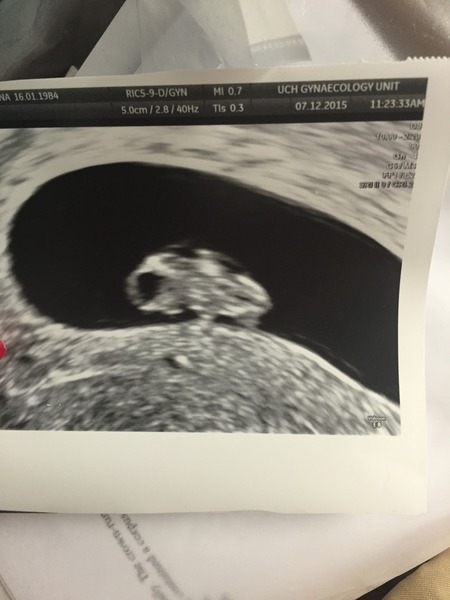

Wine- is suggest st Thomas, or UCLH. Walk in to your GP and ask to speak to a doc and they will get you your appointments- good luck. Got my 7+4day scan with a heart beat of 158- 1st baby so I cried and husband just left his mouth open through out the scan. Is anybody working?? I work 8-6 everyday and I really feel it taking its toll on me- was dizzy for 3hours today and couldn't focus on my screen- it's been tough nobody knows at work- I'm waiting till my 12weeks. Thought I'd share a pic!

Lovely pic! Congratulations!

Oh lovely picture, Jackchi! I'm working 9-5 everyday. Concentration is definitely an issue, but I don't think anyone at work has figured out why I'm a bit ditzy lately. Only 1 more week of work and then holidays in Canada! By the time I'm back in the New Year (university, so we're back to work 2nd week of January - nice long break) I should be far enough along that any nausea (which is strong this morning) will be easing.. hopefully! Are you going to be able to take it easy over the holidays?

* Lovely scn photo jackchi* thank you for sharing! I just love a scan picture! Will you get a nice break over Christmas to re-cooperate? I was thinking I would but then two dds and the festive season is probably equally as tiring! Look after yourself!

jackchi - lovely scan pick! Brightened up my morning which I am struggling through with a monster cold that will not go away!!!! Bleugh! I have nothing else useful to contribute as head so stuffy. Bleugh, bleugh, bleugh!

jackchi thanks for sharing your scan photo, I've gone all mushy! Can't wait to get mine done, think it will finally feel real then.

Nice bean Jackchi!

Awh lovely pic, Jackchi. I am so looking forward to having a scan - hoping that I can then relax for Christmas.